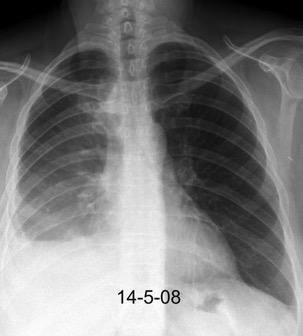

Marzo 2014: Perforación longitudinal distal secundaria a episodio de vómito (síndrome de Boerhaave). Derrame pleural izdo. que evoluciona a empiema.